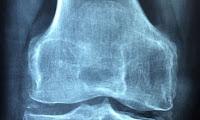

Los científicos del Campus Médico Anschutz de la Universidad de Colorado encontraron por casualidad que los ratones con artritis reumatoide inducida por anticuerpos en sus articulaciones desarrollaron lesiones espinales similares a las de la espondiloartritis axial (AxSpA) que causa la fusión del vertebrado y la curvatura o flexión de la columna vertebral. Estos mismos anticuerpos anti-colágeno también están presentes en humanos con artritis y atacan directamente el cartílago articular provocando inflamación y dolor.